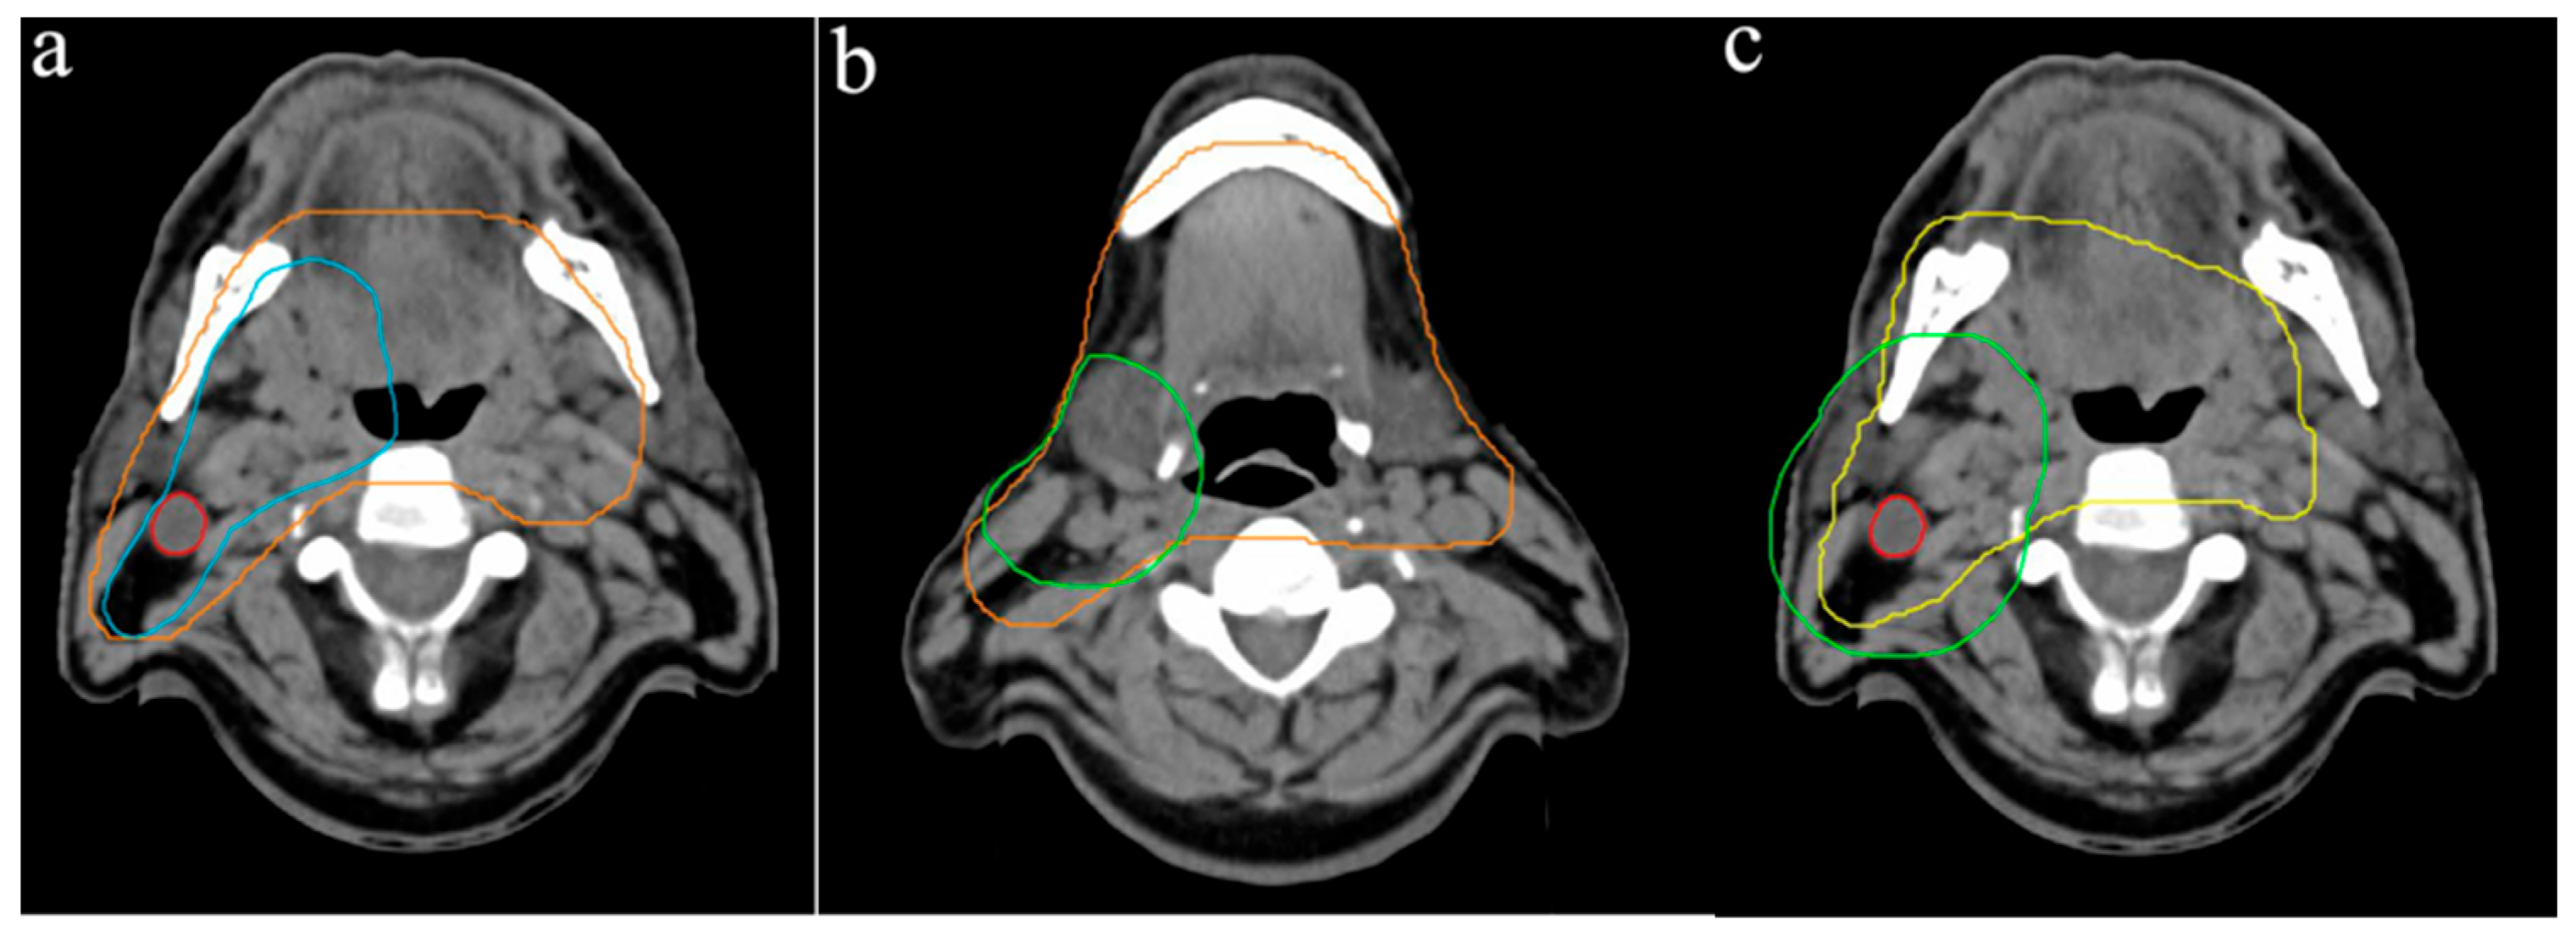

Regarding the cranial border of the PTV1, variability of up to 8 mm was observed, with seven participants selecting the same CT slice, positioned 4 mm below the floor of the sphenoid sinus (Figure 1a). The caudal PTV1 border showed greater variation, with differences of up to 20 mm, while the average lower boundary was 12 mm above the sternoclavicular joint (Figure 1b). In a representative supraclavicular lymphatic drainage slice, the PTV1 width ranged from 7.0 cm to 24.4 cm, with a mean of 16.2 cm (Figure 1c). Due to the location of tumor, the tongue was included in the PTV1 by all participants, with more than two-thirds of its volume consistently delineated.

Figure 1. Variation of PTV1 outlines: (a) cranial border in relation to the floor of the sphenoid sinus, (b) caudal border and (c) width of PTV1. Different colored lines represent the PTV outlines of the respective participants.